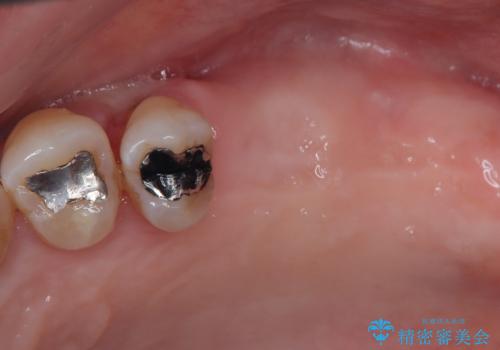

- 近医にて入れ歯が合わないためインプラント治療を希望したものの、治療期間が長く大変と聞き、当院を受診された患者様です。

レントゲンから分かるとおり、インプラント埋入に必要な骨の高さが著しく不足している状態でした。